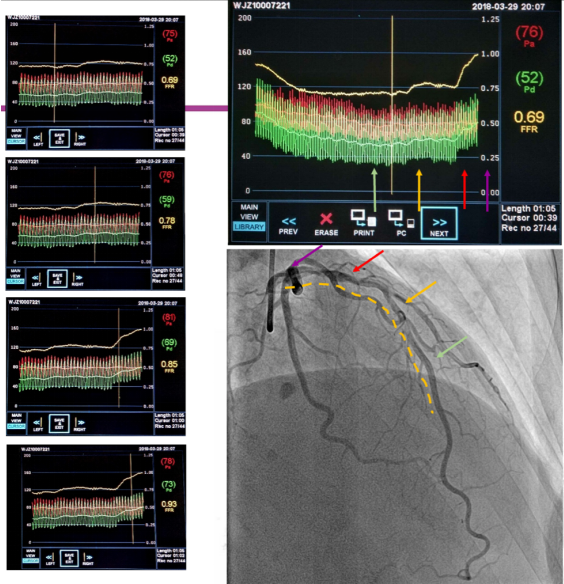

FFR检查是将带有压力传感器的导丝送到冠脉狭窄病变的远端,通过测量狭窄病变远端与近端处压力比值,评估血管狭窄是否引起心肌缺血。FFR检查可提高诊断的准确性,但存在几个不利因素:一是需要使用价格昂贵的压力导丝;二是导丝要被送至冠脉血管内,属于有创操作;三是检查过程中还需使用血管扩张药物,术中可能会出现低血压等并发症;最后是检查耗时,需要30-40分钟。

鉴于以上情况,北京清华长庚医院引进了最新的定量血流分数检查(以下简称QFR),该检查依靠冠脉造影三维重建技术和血液动力学系统,可实现精确分析狭窄冠脉血管的功能学指标,与FFR相比,是无创评估冠状动脉生理功能指标的“新标准”。同时,QFR不使用压力导丝及扩血管药物,更不需要进入体内,3-5分钟即可完成检查,检查费用相对低廉,与FFR准确性相当,便利冠心病患者接受更精准的治疗,避免更多的支架植入。目前,北京清华长庚医院已经掌握该项技术,并广泛应用在冠心病的诊断与治疗过程中,到现在已经使用OFR技术治疗100多例患者。